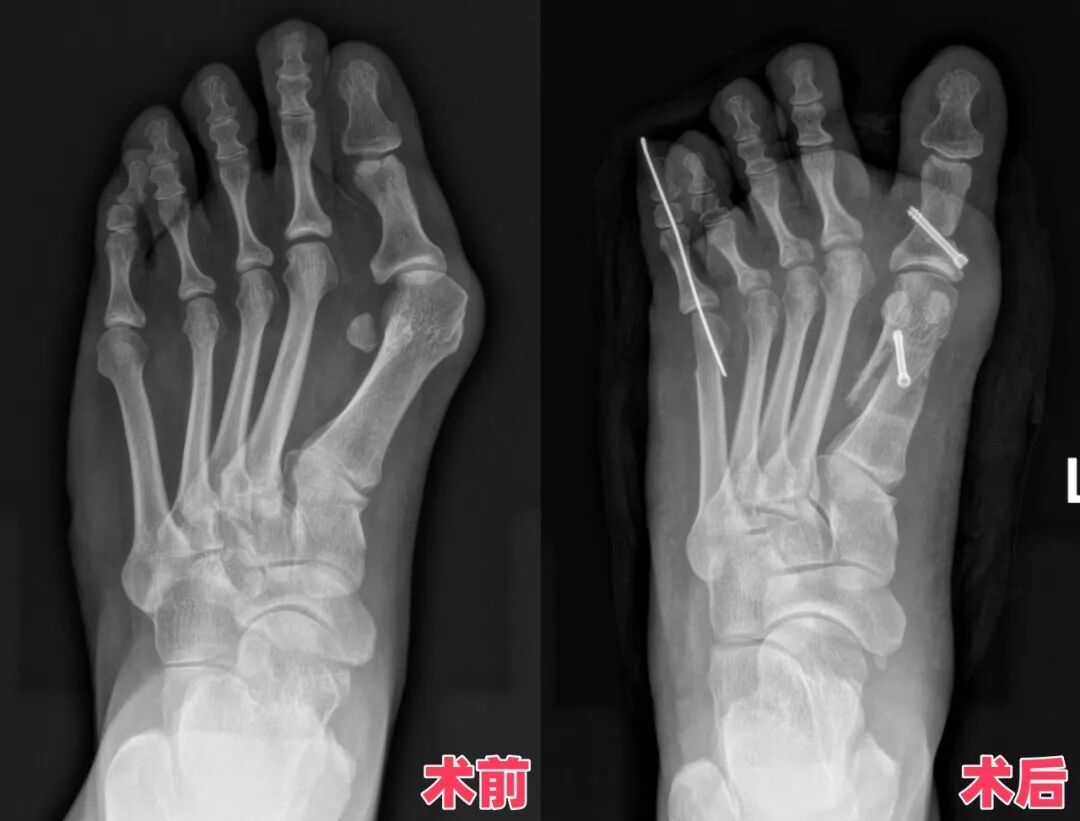

李然醫(yī)生仔細(xì)檢查后,發(fā)現(xiàn)黃女士的拇外翻已經(jīng)"升級"成重度,連小腳趾都跟著"湊熱鬧"內(nèi)翻了!保守治療已經(jīng)"愛莫能助",手術(shù)矯正才是"王牌方案"。李醫(yī)生拿著她的足部X光片仔細(xì)研究,精準(zhǔn)測量了骨頭偏移角度、韌帶松緊度,專門為她“量腳定制”了一套微創(chuàng)矯正方案!